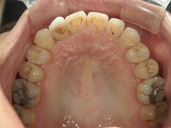

矯正歯科 治療前

矯正歯科 治療前 上顎